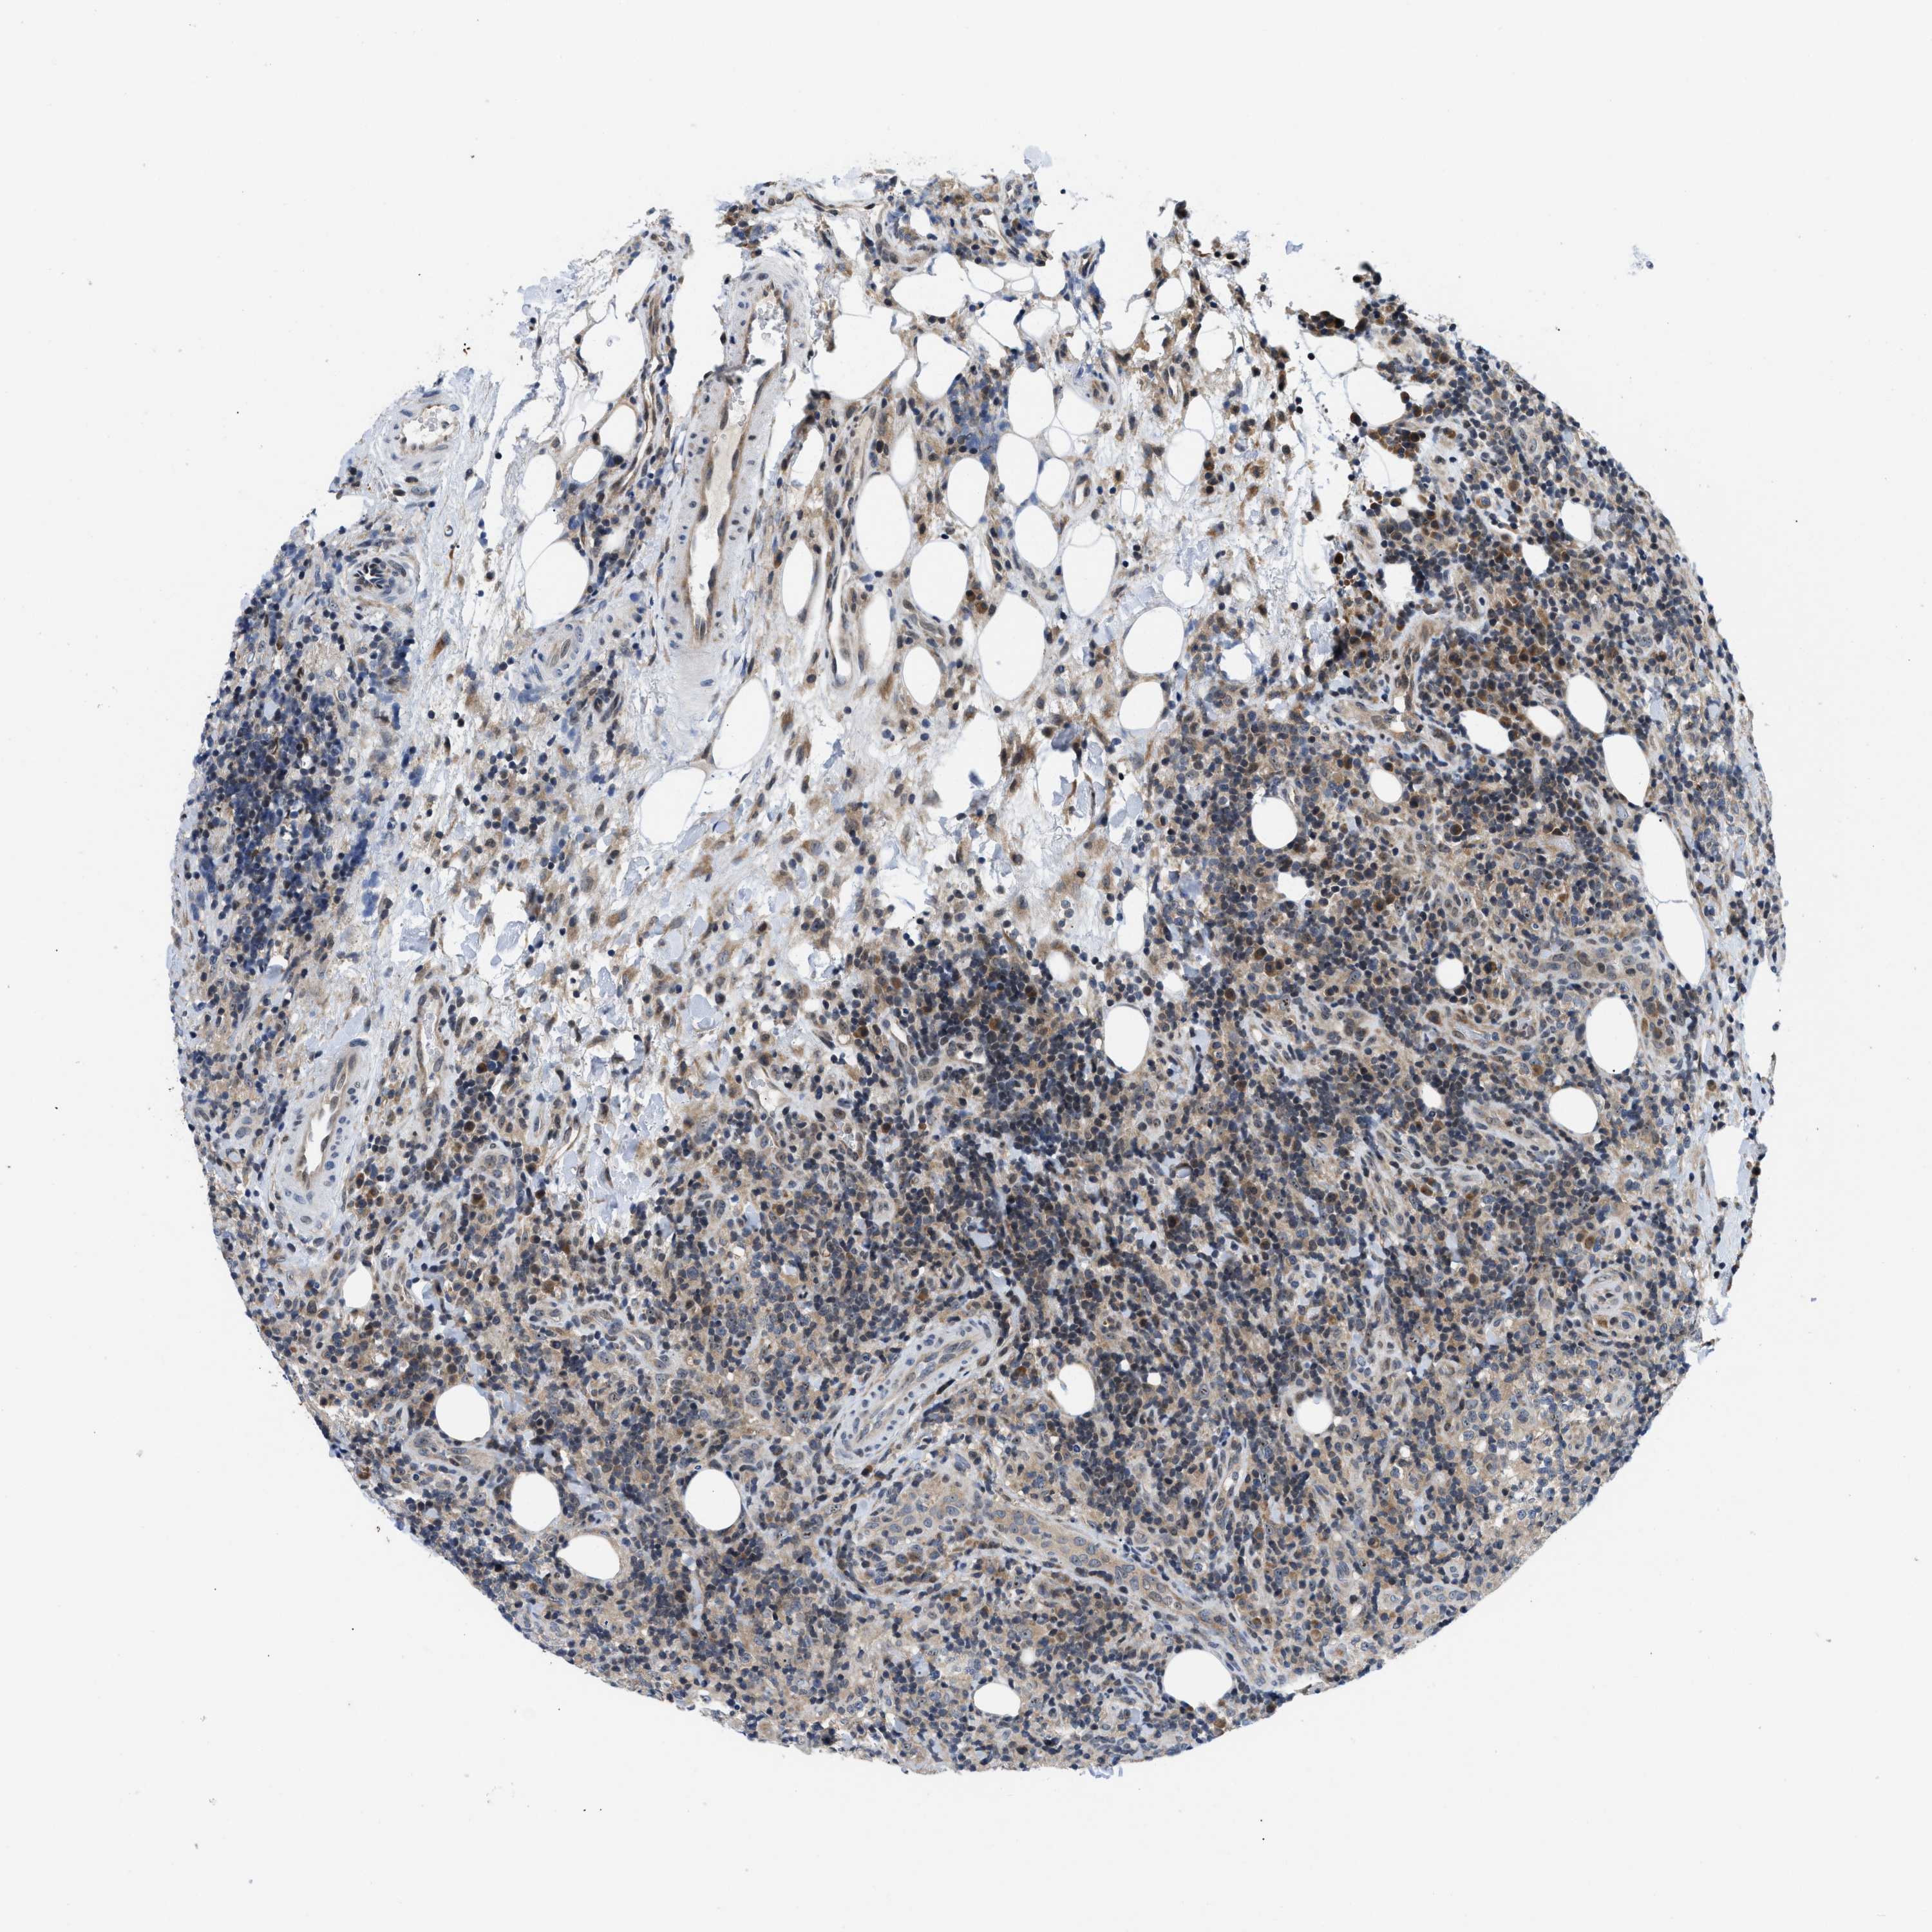

CANCER LYMPHOMA Show tissue menu

LYMPHOMA - Protein expressioni

A mouse-over function shows sample information and annotation data. Click on an image to view it in a full screen mode. Samples can be filtered based on level of antibody staining by selecting one or several of the following categories: high, medium, low and not detected. The assay and annotation is described here.

Antibody stainingi

Antibody staining in the annotated cell types in the current human tissue is reported as not detected, low, medium, or high, based on conventional immunohistochemistry profiling in selected tissues. This score is based on the combination of the staining intensity and fraction of stained cells.

Each image is clickable and will lead to virtual microscopy that enables deeper exploration of all samples and also displays staining intensity scores, fraction scores and subcellular localization as well as patient and tissue information for each sample.

Antibody HPA015788

Antibody CAB025983

Staining

High

Medium

Low

Not detected

Intensity

Strong

Moderate

Weak

Negative

Quantity

>75%

75%-25%

<25%

None

Location

Nuclear

Cytoplasmic/membranous

Cytoplasmic/membranous,nuclear

Hodgkin's disease, NOS

Malignant lymphoma, non-Hodgkin's type, High grade

Malignant lymphoma, non-Hodgkin's type, Low grade